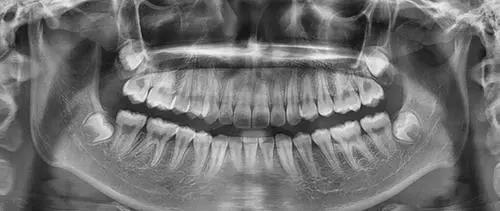

五、为什么根管治疗需要拍多张牙片?

根管治疗时,拍牙片是很有必要的,并且至少要保证3张牙片。

第一张在治疗前,帮助医生了解牙根的基本情况,制定治疗计划;

第二张在治疗中,帮助医生了解治疗情况,如根管预备是否到位等,并制定下一步治疗方案;

第三张是在治疗结束后,帮助判定根管充填质量,发现问题及时补救。